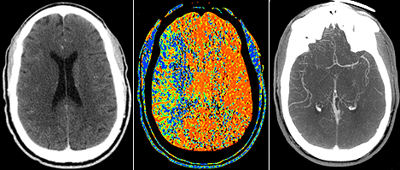

A patient suffering a right brain stroke as shown on CT, CT perfusion, CT Angiography.

Keep in mind that the radiation doses used in medical radiological imaging examinations like computed tomography (CT) and X-ray scans are much lower than those used in radiation oncology, which uses radiation as a therapy to treat cancer. Radiology (imaging) and radiotherapy (cancer treatment) are quite different.

• Guiding treatment of common conditions such as injury, cardiac disease and stroke